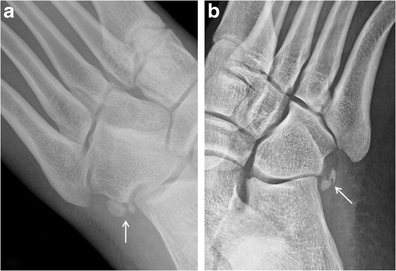

Os intermetatarseum. Oblique radiographs of the foot from two different patients show rounded (a) and spindle (b) configurations of the os intermetatarseum (arrows) located between the base of the first and second metatarsals. This may sometimes be mistaken for a bone fragment secondary to a remote trauma